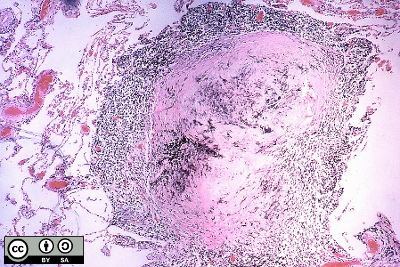

- Silicotic nodules are a recognisably distinct lung reaction to crystalline silica. They comprise a central hyaline core surrounded by whorls of collagen, as illustrated.

- Using polarised light refractile silica particles may be seen in the nodule.